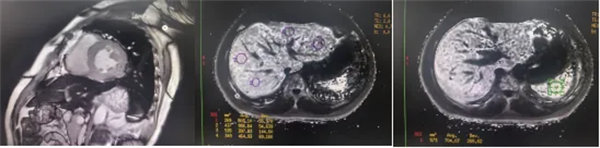

肝臟和脾臟信號改變 矢狀位梯度回波定位圖像可顯示肝臟和脾臟信號降低,提示肝脾鐵沉積,T2*>6.3及R2*>160/s表現中度鐵過載。